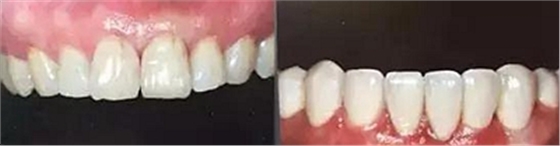

上下前牙正面影像

構(gòu)圖包含4-6顆前牙,中切牙為對(duì)焦中心

采用黑背景

拍攝比例:1:1.8,光圈f38,快門速度1/125,閃光強(qiáng)度M/4